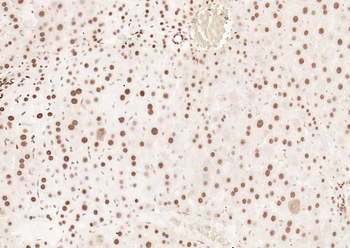

50 μl, 100 μlPhospho-Smad3 (Thr179) Rabbit Polyclonal Antibody [orb313112]

FC, ICC, IF, IHC-Fr, IHC-P

Bovine, Canine, Equine, Porcine, Sheep

Human, Mouse, Rat

Rabbit

Polyclonal

Unconjugated

100 μl, 200 μl, 50 μlSMAD7 Rabbit Polyclonal Antibody [orb500819]